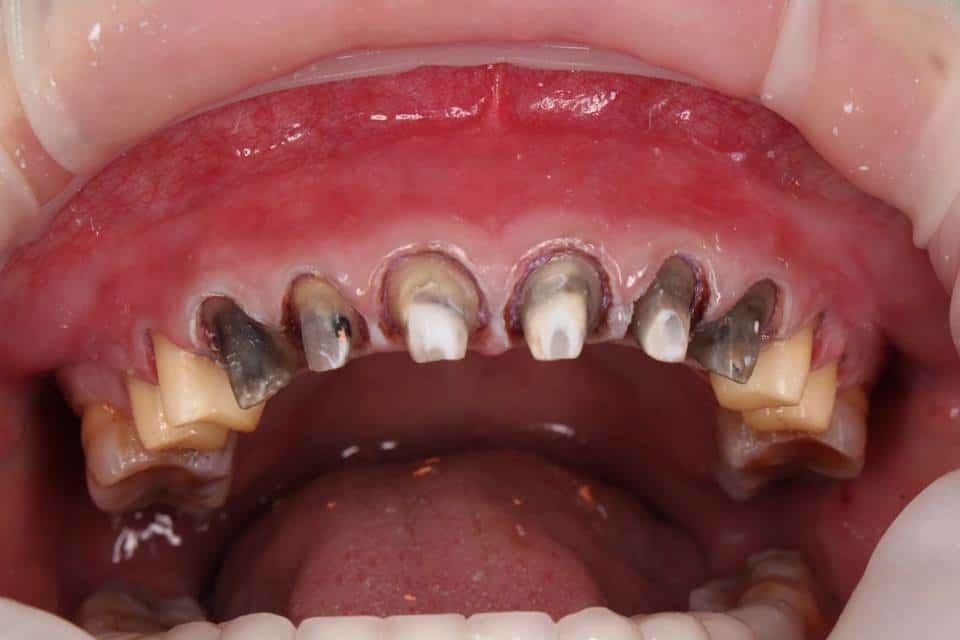

- Tụt lợi và lộ chân răng: Do phản ứng viêm kéo dài hoặc phục hình sai kỹ thuật, nướu rút lên làm lộ phần cổ răng hoặc sứ, gây mất thẩm mỹ và ê buốt.

- Viêm tủy, chết tủy: Việc mài răng quá mức hoặc không kiểm soát sẽ làm tổn thương đến phần tủy bên trong, gây đau nhức, nhiễm trùng, thậm chí mất răng vĩnh viễn.

- Viền sứ đen xỉn, lộ kim loại – đặc biệt là với dòng sứ kim loại rẻ tiền, gây mất thẩm mỹ nghiêm trọng.